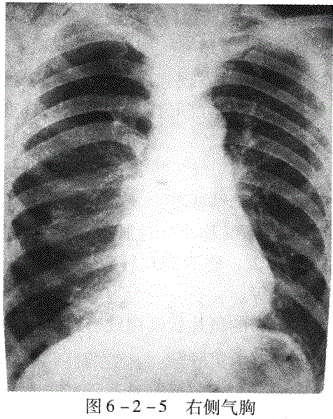

1.气胸(6-2-5) 空气进入胸腔则形成气胸。空气进入胸腔的途径:壁层胸膜破

裂,脏层胸膜破裂。X线表现为肺向肺门方向压缩,其与胸壁间出现透明的含气区,其内不见肺纹理,纵隔向健侧移位,患侧膈下降,肋间隙增宽。健侧肺可有代偿性肺气肿。

青年男性,突发胸痛4小时。胸像示右侧肋间隙增宽,右肺向肺门方向压缩,其与胸壁间出现透明的含气区,其内不见肺纹理。